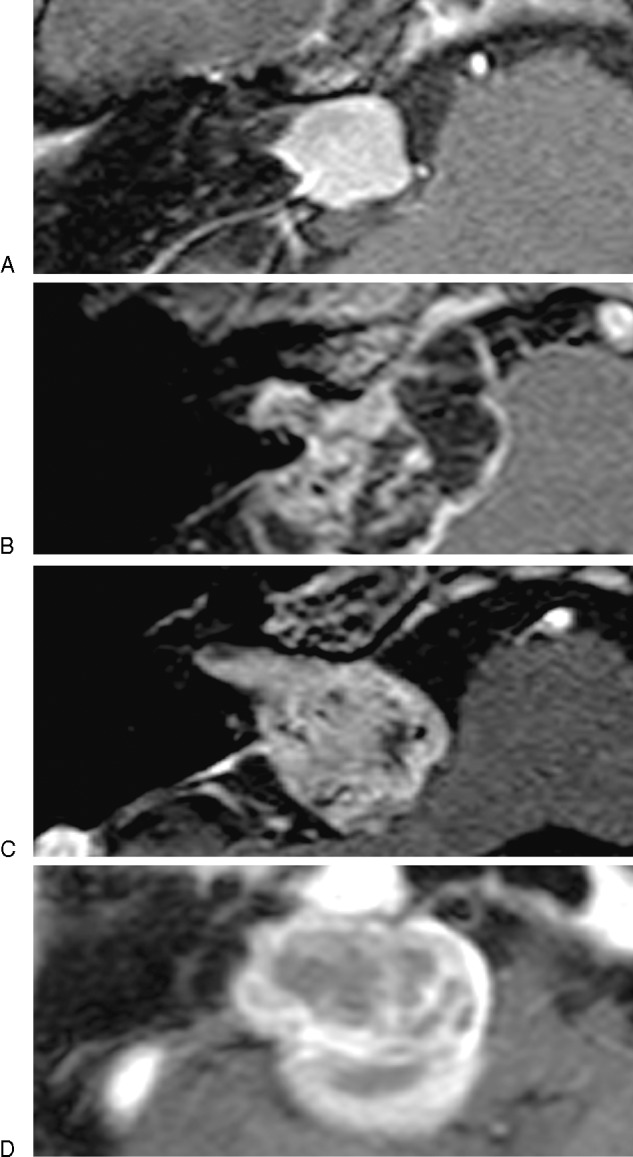

Hearing function was considered useful in patients with pure tone average better than 50 dB and speech discrimination score better than 50% according to Gardner-Robertson grading system.11 Facial nerve function was evaluated with Yanagihara grading system.12 The classification of tumor localization in the IAC on MR images was grade 1 (tumor located up to the mid-portion of the IAC), grade 2 (tumor located over the mid-portion of the IAC), grade 3 (tumor located up to the fundus of the IAC), and grade 4 (tumor located up to the fundus of the IAC with bony destruction) (Fig. 1A–D). Residual tumor in the IAC on MR images was evaluated as grade A (remnant tumor not observed in the IAC), grade B (remnant tumor in the IAC observed slightly in the fundus), grade C (remnant tumor in the IAC observed up to the mid-portion of the IAC), and grade D (remnant tumor in the IAC located beyond the mid-portion of the IAC) (Fig. 2A–D).

Figure 1.

The classification of tumor localization in the internal auditory canal (IAC) on magnetic resonance images was grade 1: tumor located up to the mid-portion of the IAC (A), grade 2: tumor located over the mid-portion of the IAC (B), grade 3: tumor located up to the fundus of the IAC (C), and grade 4: tumor located up to the fundus of the IAC with bony destruction (D).